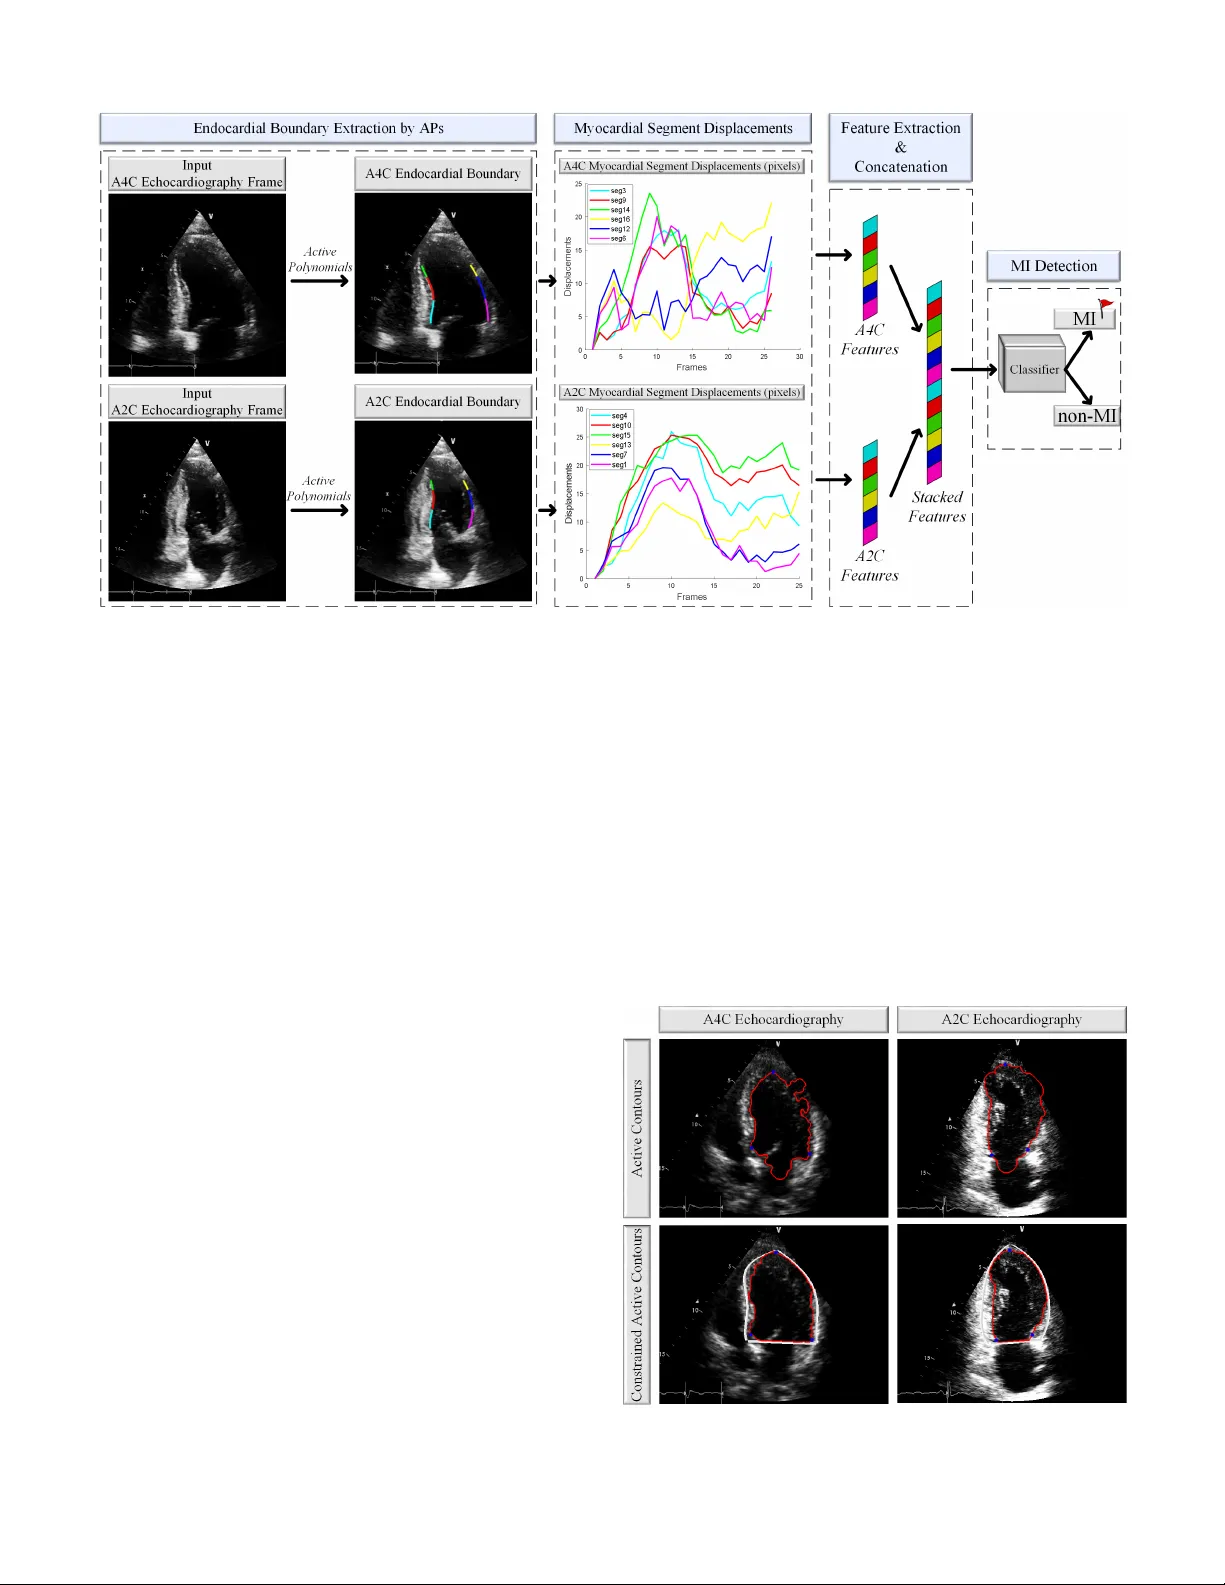

본 연구는 심근경색(MI) 조기 진단을 위해 심장의 두 가지 주요 단면인 A4C(4‑chamber)와 A2C(2‑chamber) 영상을 결합한다. 활성 다항식(Active Polynomials, APs)으로 좌심실(LV) 내벽을 정밀히 추적·분할하고, 각 12개 세그먼트의 변위 곡선에서 최대 변위를 특징량으로 추출한다. 이 특징을 다중 머신러닝 분류기(Decision Tree, Random Forest, k‑NN, SVM, 1D‑CNN)에 입력…

본 논문은 심근경색(MI) 조기 진단을 위한 새로운 자동화 파이프라인을 제시한다. 연구 배경으로는 MI가 전 세계 사망 원인 1위이며, 조기 진단이 치료 성공률을 크게 높인다는 점을 들었다. 기존 진단 방법인 ECG·혈액 마커는 민감도가 낮고, 결과가 나오기까지 시간이 오래 걸린다. 반면 2차원 초음파(심초음파)는 저비용·실시간·비침습이라는 장점으로 조기 평가에 적합하지만, 인간 전문가가 RWMA(지역 벽운동 이상)를 시각적으로 판단하는 과정은 주관적이며, 특히 단일 뷰(A4C 혹은 A2C)만으로는 병변이 보이지 않을 위험이 있다. 이에 저자들은 두 가지 주요 기여를 한다. 첫째, A4C와 A2C 두 뷰를 동시에 활용해 총 12개의 심근 세그먼트를 분석함으로써 기존 단일‑뷰 접근법의 한계를 극복한다. 둘째, ‘활성 다항식(Active Polynomials, APs)’이라는 새로운 경계 추적 기법을 도입한다. APs는 Ridge Polynomial으로 잡음이 많은 영역을 사전 제약하고, Chan‑Vese 기반 활성 컨투어를 적용해 내강 경계를 정확히 추출한다. 이후 4차 다항식 피팅을 통해 부드러운 연속 곡선을 얻어, 변위 측정의 신뢰성을 확보한다. 경계가 확보되면 좌심실을 미국 심장학회(AHA) 17‑segment 모델에 따라 12개의 분석 가능한 세그먼트로 나눈다(세그먼트 17은 제외). 각 세그먼트에 대해 5개의 등간격 포인트를 선택하고, 한 심장 주기 동안 평균 변위 Dₛₖ(t)를 계산한다. 변위 곡선은 정상에서는 수축기·이완기 전형적인 상승·감소 패턴을 보이며, MI 환자에서는 해당 세그먼트의 최대 변위가 현저히 감소한다. 저자들은 이 최대 변위값을 피처로 채택하고, A4C와 A2C에서 얻은 12개의 피처를 연결해 24차원 피처 벡터를 만든다. 다음 단계에서는 다양한 머신러닝 및 딥러닝 분류기를 비교한다. Decision Tree, Random Forest, k‑Nearest Neighbour, Support Vector Machine, 그리고 1D‑Convolutional Neural Network(1D‑CNN)를 사용했으며, 교차 검증을 통해 최적 모델을 선정한다. 실험 결과, Random Forest와 1D‑CNN가 가장 높은 성능을 보였으며, 전체 데이터셋(260개 영상, 130명 MI 환자·130명 정상)에서 90.91%의 민감도와 86.36%의 정밀도를 달성했다. 이는 기존 단일‑뷰 기반 임계값(Threshold) 방식보다 크게 향상된 수치이며, 다중‑뷰 융합이 실제 임상 상황에서 놓칠 수 있는 RWMA를 효과적으로 포착함을 증명한다. 또한, 저자들은 HMC‑QU라는 새로운 벤치마크 데이터셋을 구축하고 공개하였다. 데이터는 Kaggle에 업로드돼 누구나 다운로드·재현이 가능하며, 코드 역시 GitHub(https://github.com/degerliaysen/MultiEchoAI)에서 제공한다. 이는 초음파 기반 MI 진단 연구의 투명성과 확장성을 크게 높이는 조치이다. 논문의 제한점으로는 피처가 최대 변위 하나에만 의존해 시간적 동역학 전체를 활용하지 못한다는 점, 12세그먼트만을 사용해 심근 전체를 완전하게 커버하지 못한다는 점, 그리고 현재는 두 뷰만을 고려했으므로 장축·단축 등 추가 뷰를 포함하면 더욱 강인한 모델이 될 가능성이 있다는 점을 언급한다. 향후 연구에서는 변위 곡선의 주파수·스펙트럼 분석, 시계열 딥러닝(LSTM, Transformer) 모델 적용, 그리고 ECG·바이오마커와의 멀티‑모달 융합을 통해 진단 정확도와 임상 적용성을 높일 수 있을 것으로 기대한다.